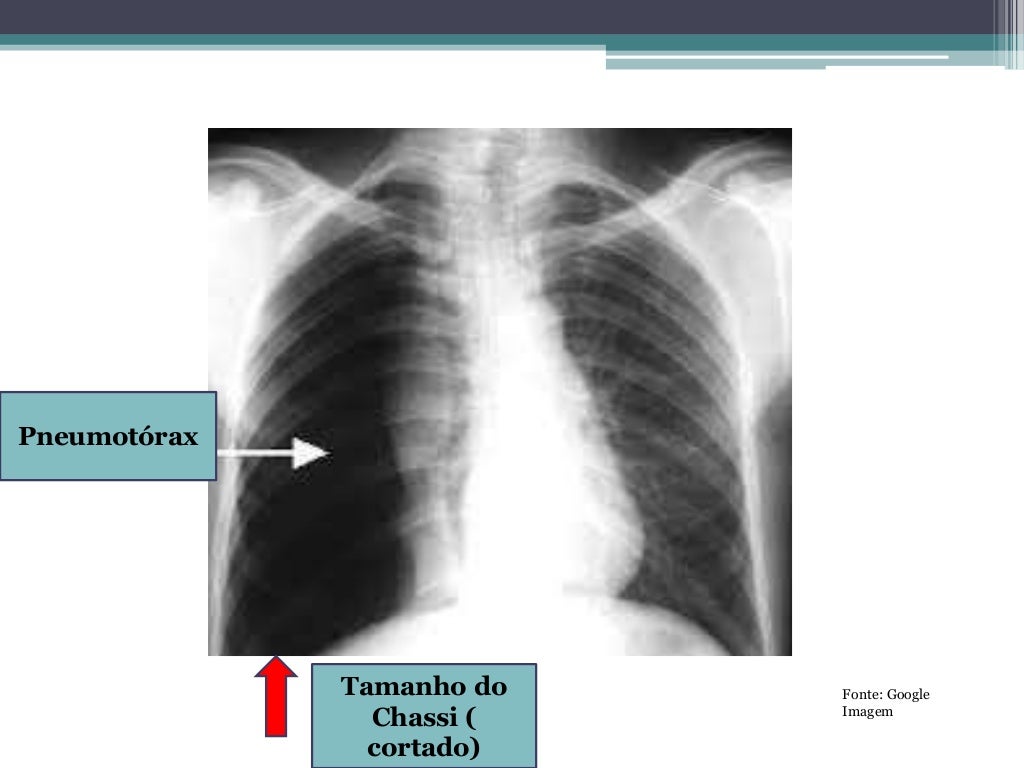

Raio x de Tórax Casos Clinicos Pneumotórax simples l Dr Ramoniê Slides Raio X este modelo é inspirado em ilustrações de raios x, com cor azul, tradicionalmente associados a questões de saúde, pois transmite confiança. introdução em 1895, o físico alemão wilhelm conrad roentgen publicou estudos observando a emissão de “luz” em. Scribd is the world's largest social reading and. começa com os métodos antigos de diagnóstico clínico e a descoberta. Slides Raio X.